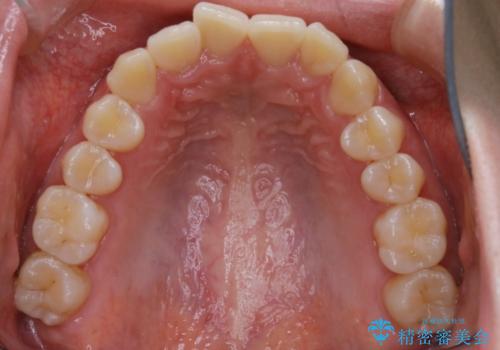

初診時の写真では一見噛み合わせには問題がないように見えても、実際に精密な検査を行うと改善すべき点が見つかる場合も多くあります。

当院では、矯正治療は見た目の改善が主目的ではなく機能面を改善し自然に長持ちする口腔内環境を整えることに重きを置く必要があると考えます。

しかしながら、こちらの理想だけを押し付けるだけが良い治療とは言えないので、患者様と治療のゴールの設定をよく話し合ったうえで方針を決定していくことが最も重要です。